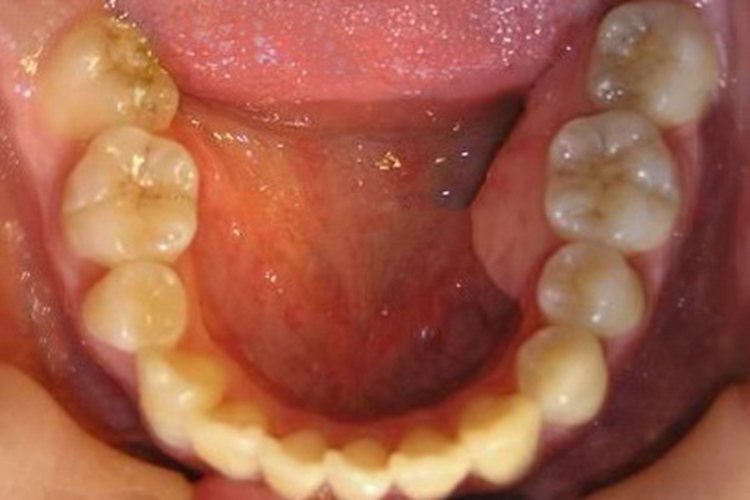

可表现为在患牙的舌腭侧牙龈形成椭圆形或半球状的肿胀突起,牙龈发红、水肿,表面光亮。脓肿的早期疼痛较明显,后期疼痛稍减轻,此时可有脓液溢出。